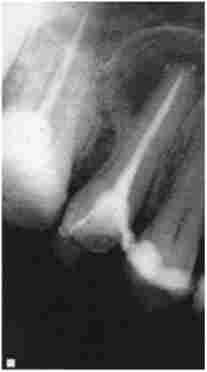

Мал. 10.9. Повторне лікування. Діагноз: К04.8 «Коренева кіста 1.5 зуба». Коренева пломба НЕ гомогенна, не доходить до верхівки кореня

Повторне лікування. Продовження. Видалення кореневої пломби і рентген-контроль проходження кореневого каналу зуба 1.5

Мал. 10.10. Повторне лікування. Продовження. Видалення кореневої пломби і рентген-контроль проходження кореневого каналу зуба 1.5

Повторне лікування. Продовження. Контроль пломбування кореневого каналу зуба 1.5. Запломбований магістральний канал і відгалуження у верхівки кореня; запальний набряк зменшився

Мал. 10.11. Повторне лікування. Продовження. Контроль пломбування кореневого каналу зуба 1.5. Запломбований магістральний канал і відгалуження у верхівки кореня; запальний набряк зменшився,

контури кісти чіткі